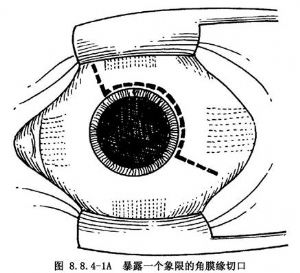

10.2 2.結膜切開並暴露鞏膜

多采用角膜緣切口(圖8.8.4-1A、B),也可距角膜緣4~6mm切口。用剪刀剪開結膜及球筋膜後,貼鞏膜表面鈍性分離。鞏膜暴露多采用眼外肌牽引線法。先以彎剪刀分離直肌止端兩側及表麪筋膜組織。用斜視鉤遊離並鉤起直肌,1號絲線穿過直肌下(圖8.8.4-2)。如暴露1個象限鞏膜,牽拉該象限兩側直肌牽引線,配合開瞼鉤即可(圖8.8.4-3)。如暴露的鞏膜部位非常靠後,或暴露直肌下的鞏膜,有時要暫時切斷某條直肌。斷肌肉前,先預置肌肉縫線(圖8.8.4-4)。